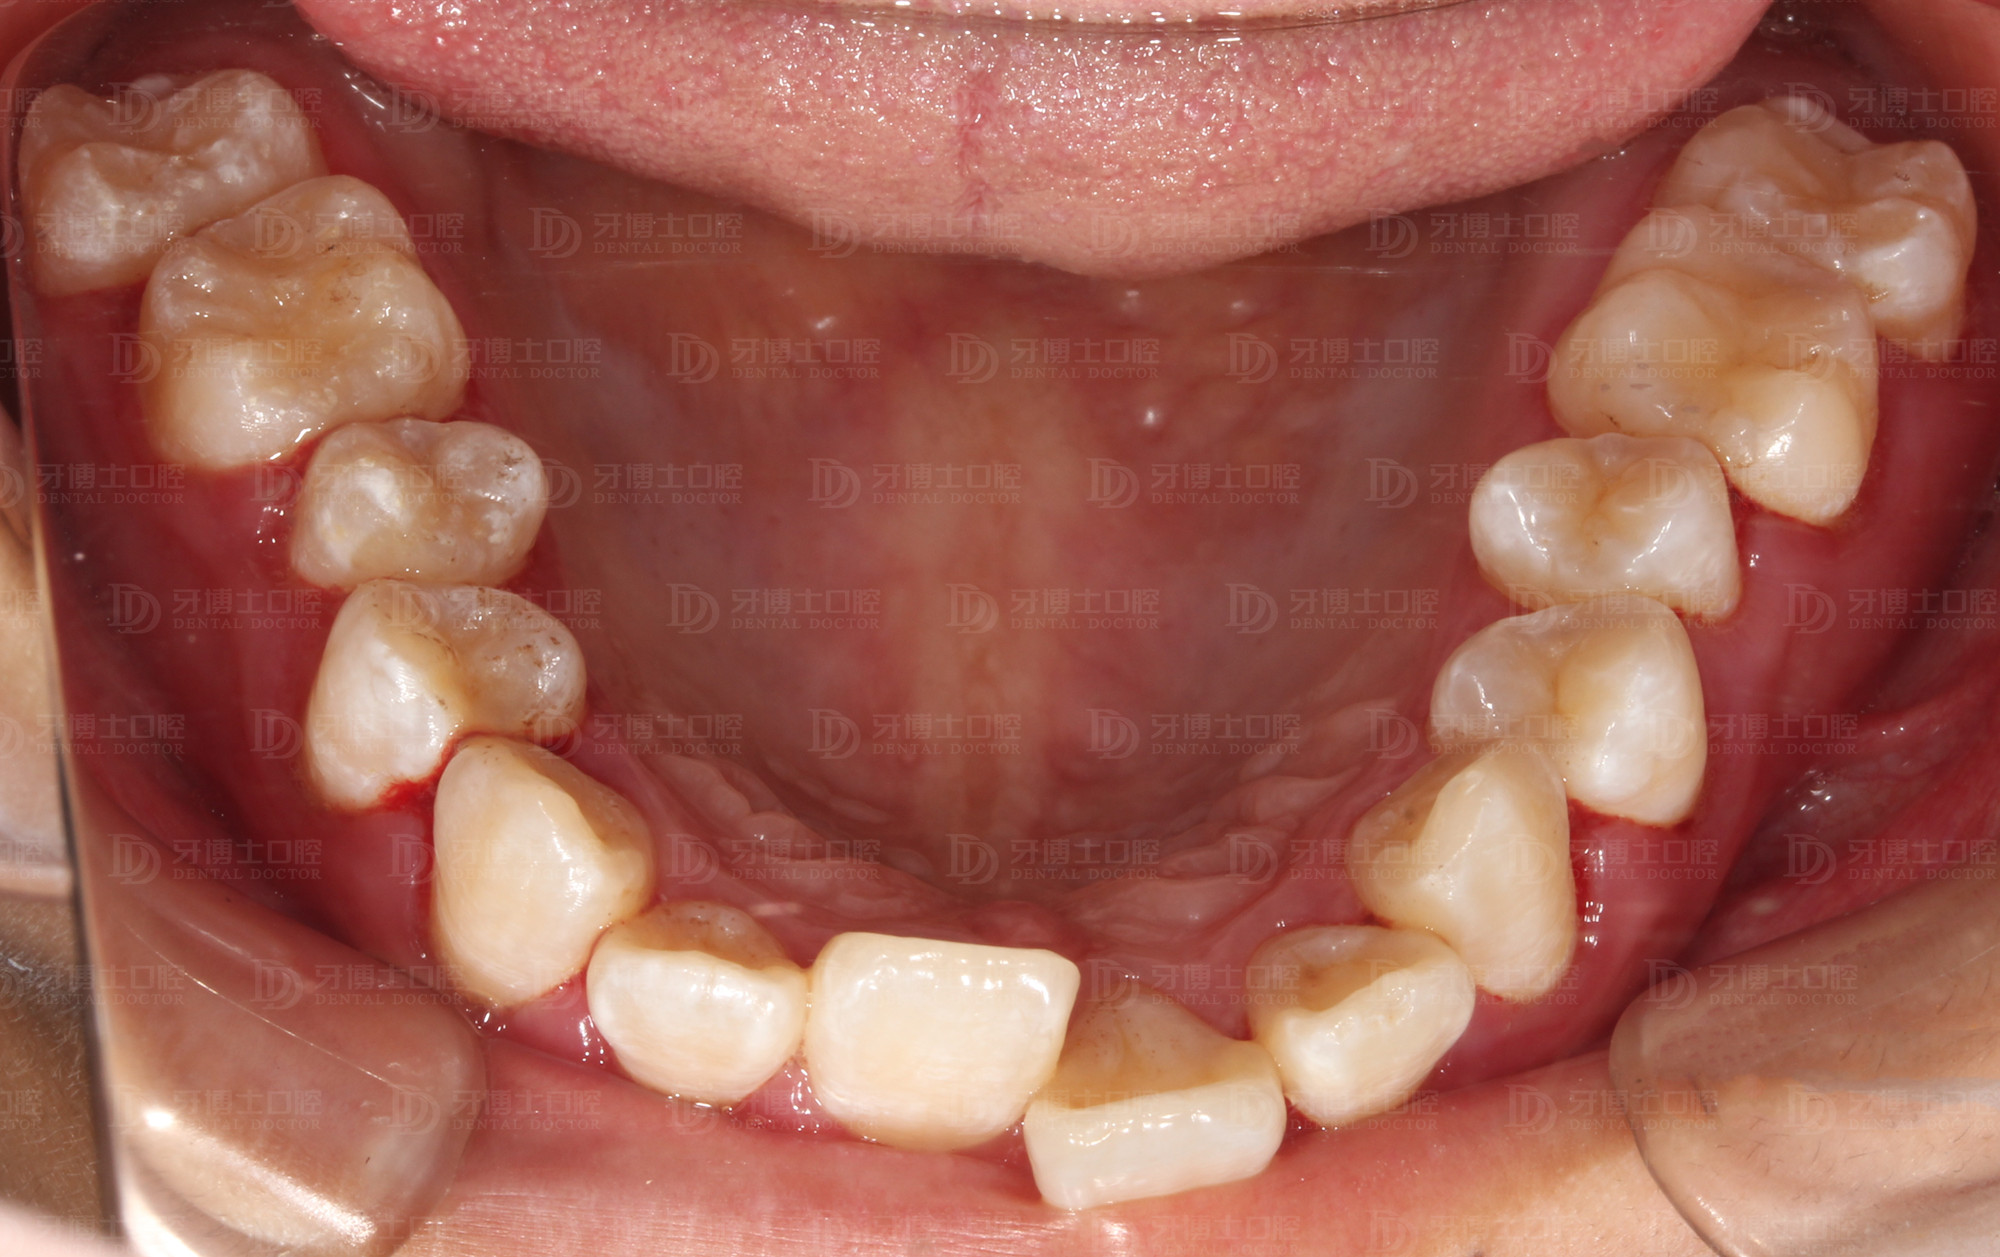

矫正前

牙列不齐,并有牙龈炎、牙结石,刷牙时会出血,同时美观度较差,影响容貌。